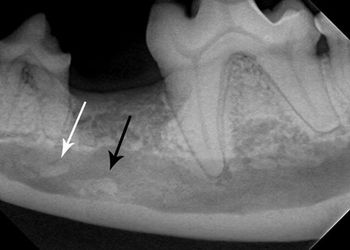

Mandibular and maxillary trauma can be difficult to evaluate and treat. Here are some tips that can help you streamline your diagnostics and improve your outcomes.

You see a possible lesion on a veterinary patient's dental film-here's how to tell if it's the real thing.

Intraoral radiography can help identify this pathology in your patients-and guide you toward the next step in your treatment plan.